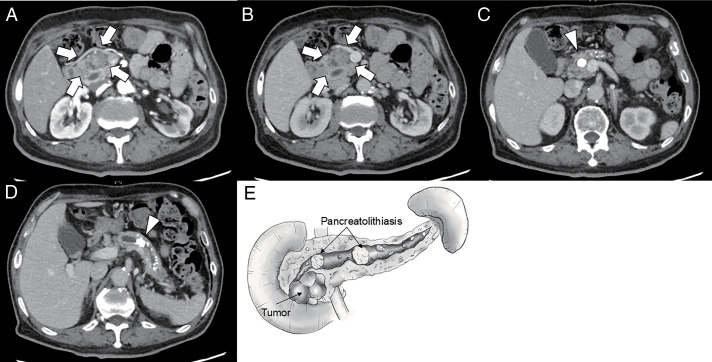

Case presentation: A man in his 70s was referred to our hospital with a pancreatic head tumor. He had been treated for CP, diabetes mellitus, and chronic kidney disease. Imaging revealed a cystic pancreatic head tumor with a solid component that was histologically confirmed as IPMC. In addition, multiple calcifications suggestive of PL were observed in the pancreatic body and tail. SSPPD and LPJ were performed to excise the PL as much as possible and preserve the residual pancreatic function. The postoperative course was uneventful, and no abdominal symptoms or tumor recurrences were observed for approximately 8 months after surgery.